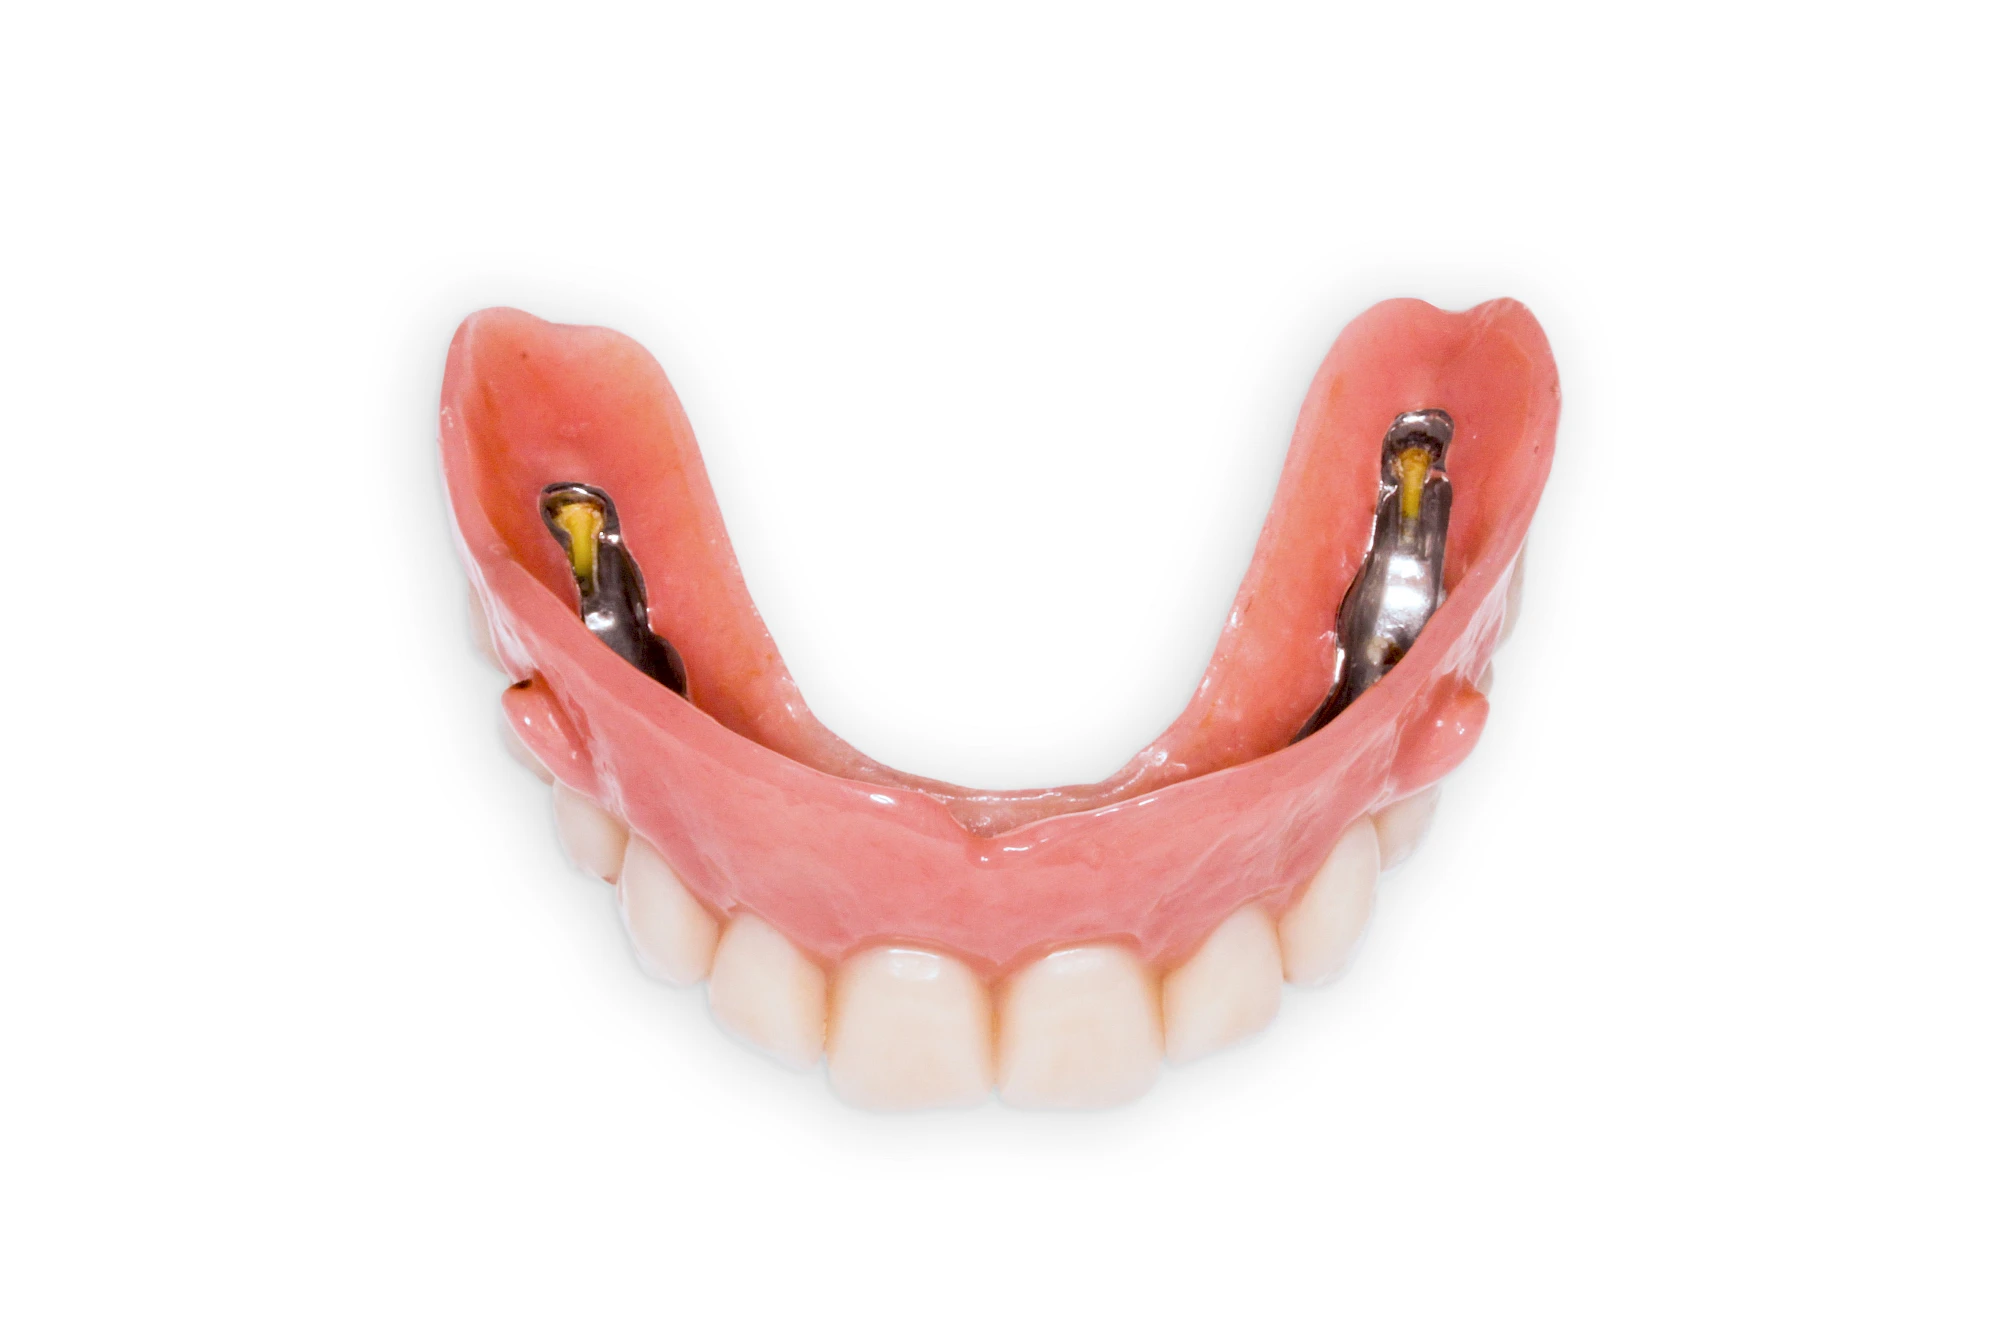

Implantate: Prothesen

Bei herausnehmbaren Prothesen werden Implantate eingesetzt, um den Halt und den Tragekomfort der Prothesen zu verbessern. Dazu kommen verschiedene Verbindungselemente zum Einsatz:

- Teleskope

- Kugelköpfe

- Tellerförmige Lokatoren

- Stege

- Magnete (selten)

Neben rein implantat-getragenen zahnärztlichen Versorgungen werden bei herausnehmbaren Prothesen Implantate auch in Sinne einer "strategischen Pfeilervermehrung" ergänzend zu eigenen Zähnen zur Verankerung eines Zahnersatzes genutzt.

Varianten zur Verankerung von abnehmbarem Zahnersatz auf Implantaten